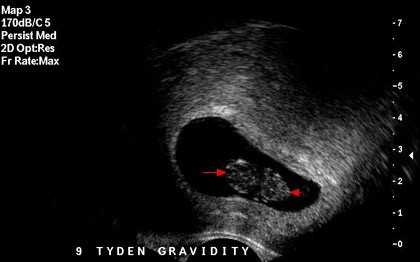

Fakt, że będę mieć duże problemy z zajściem w ciążę, wiem od lat. Dokładnie od 15 lat - odkąd zaczęłam menstruować. Ginekolog zdiagnozował u mnie zespół policystycznych j...